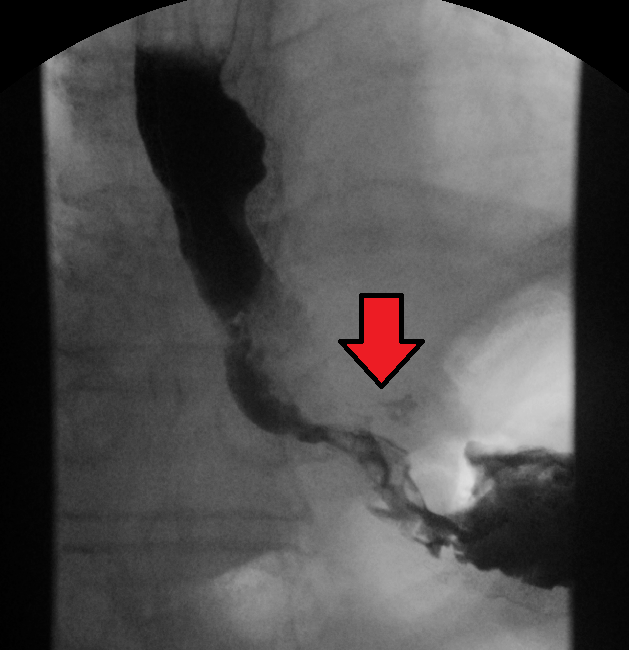

식도암 진단은 주로 내시경 검사를 통해 이루어진다. 바륨 삼킴 검사나 바륨 식사 검사에서 폐쇄성 종양을 의심할 수 있지만, 내시경 검사가 더 정확하다. 내시경 검사는 식도위십이지장내시경검사라고도 불리며, 빛과 카메라가 달린 유연한 관을 식도로 넣어 식도 벽을 검사하는 방식이다. 이 과정에서 의심스러운 병변의 조직을 채취하여 조직학적으로 악성 종양 여부를 확인한다.[140][141]

4. 1. 임상적 평가

바륨 삼킴 검사나 바륨 식사 검사에서 폐쇄성 종양을 의심할 수 있지만, 진단은 내시경을 이용한 검사로 하는 것이 가장 정확하다. 내시경 검사는 광원과 카메라가 달린 유연한 관을 식도로 통과시켜 식도벽을 검사하는 것으로, 식도위십이지장내시경검사라고 한다. 그런 다음 의심스러운 병변의 조직을 채취하여 악성 징후가 있는지 조직학적으로 검사한다.[140][141]암이 얼마나 퍼졌는지 평가하려면 추가 검사가 필요하다. 흉부, 복부 및 골반의 컴퓨터 단층 촬영(CT)을 통해 암이 인접 조직이나 멀리 떨어진 장기(특히 간 및 림프절)로 퍼졌는지 여부를 평가할 수 있다. CT 스캔의 민감도는 일반적으로 1cm 보다 큰 종괴(예: 림프절 비대 또는 관련 장기)를 감지하는 능력에 의해 제한된다.[142] 양전자 방출 단층 촬영(PET)은 질병의 범위를 추정하는 데 사용되며 CT 단독보다 더 정확한 것으로 간주된다.[143] 새로운 검사 기구인 PET/MR은 PET/CT와 비교하여 타당성이 높고 상관관계가 좋은 수술 전 병기 결정에서 유망한 결과를 보여주었다.[144] 환자에 대한 방사선량을 낮추면서 조직 분화를 향상시킬 수 있다. 식도 내시경 초음파는 종양의 침범 수준과 국소 림프절로의 전이 가능성에 관한 병기 정보를 제공할 수 있다.